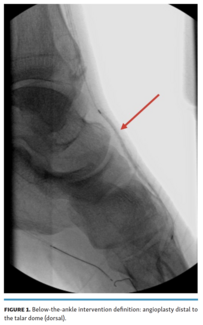

The objective of this study was to evaluate the safety and efficacy of below-the-ankle intervention in the office-based setting for treatment of chronic limb-threatening ischemia.

The purpose of this study was to investigate the effect of below-the-ankle (BTA) angioplasty on angiographic pedal arch patency and its association with clinical outcomes in patients with chronic critical limb ischemia (CLI).